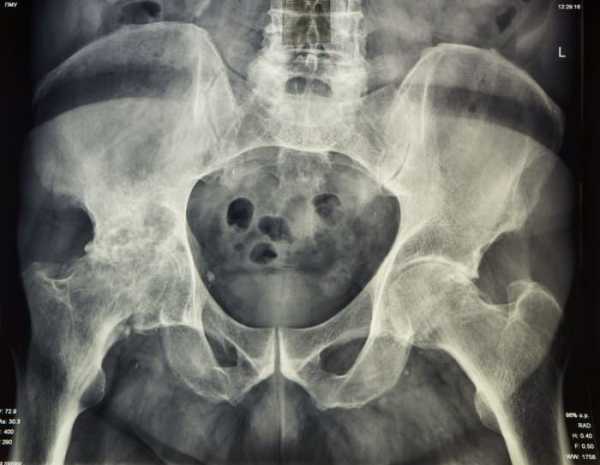

Чтобы правильно определить, почему болит нога, врач проводит дифференциальную диагностику. Для этого использует такие методы исследования:

- МРТ позвоночника, таза, бедра;

- рентгенография;

Диагностика при болях в зоне тазобедренного сустава в первую очередь направлена на установление виновника мучительных ощущений при ходьбе. Для этого пациенту назначают ряд лабораторных и инструментальных исследований:

- рентгенографию в 2 проекциях;

- КТ и МРТ таза; подробнее про МРТ суставов→

Для диагностики используют лабораторные методы, рентген-обследование, МРТ. В крови определяется умеренный лейкоцитоз, увеличение СОЭ. Рентгенологическая картина характеризуется появлением периостальной воспалительной реакции и остеофитами.

Ответом на вопрос: «что делать, когда болит тазобедренный сустав?» может служить то, что для начала необходимо проконсультироваться с узкими специалистами (невролог, травматолог-ортопед, ревматолог). Также необходимо знать, что при появлении такой жалобы обследование проводится с помощью следующих методов:

- Рентгенологическое исследование сустава с обеих сторон;

- МСКТ И МРТ с контрастированием, так и без него. В первом случае это выполняется при подозрении на саркому кости или ее распад в костной ткани;